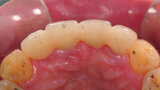

Fig. 14: Provisional restoration on the model.